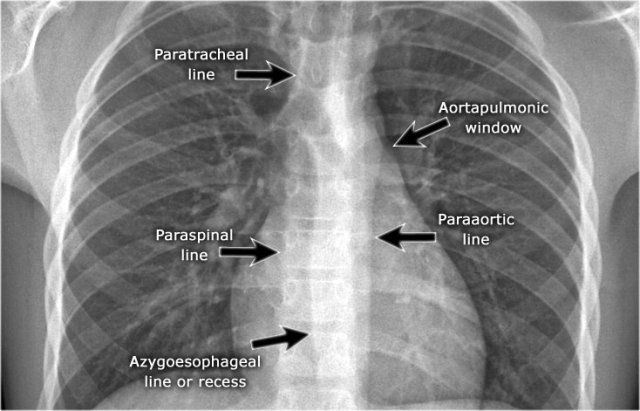

On the PA chest-film it is important to examine all the areas where the lung borders the diaphragm, the heart and other mediastinal structures.

At these borders lung-soft tissue interfaces are seen resulting in a:

- Line or stripe - for instance the right para tracheal stripe.

- Silhouette - for instance the normal silhouette of the aortic knob or left ventricle

These lines and silhouettes are useful localizers of disease, because they can be displaced or obscured with loss of the normal silhouette. This is called the silhouette sign, which we will discuss later.

The paraspinal line may be displaced by a paravertebral abscess, hemorrhage due to a fracture or extravertebral extension of a neoplasm.

Widening of the paratracheal line (> 2-3mm) may be due to lymphadenopathy, pleural thickening, hemorrhage or fluid overload and heart failure.

Displacement of the para-aortic line can be due to elongation of the aorta, aneurysm, dissection and rupture.

An important mediastinal-lung interface to look for is the azygoesophageal line or recess (arrow).

Mediastinal lines

Mediastinal lines or stripes are interfaces between the soft tissue of mediastinal structures and the lung.

Displacement of these lines is helpful in finding mediastinal pathology, as we have discussed above.